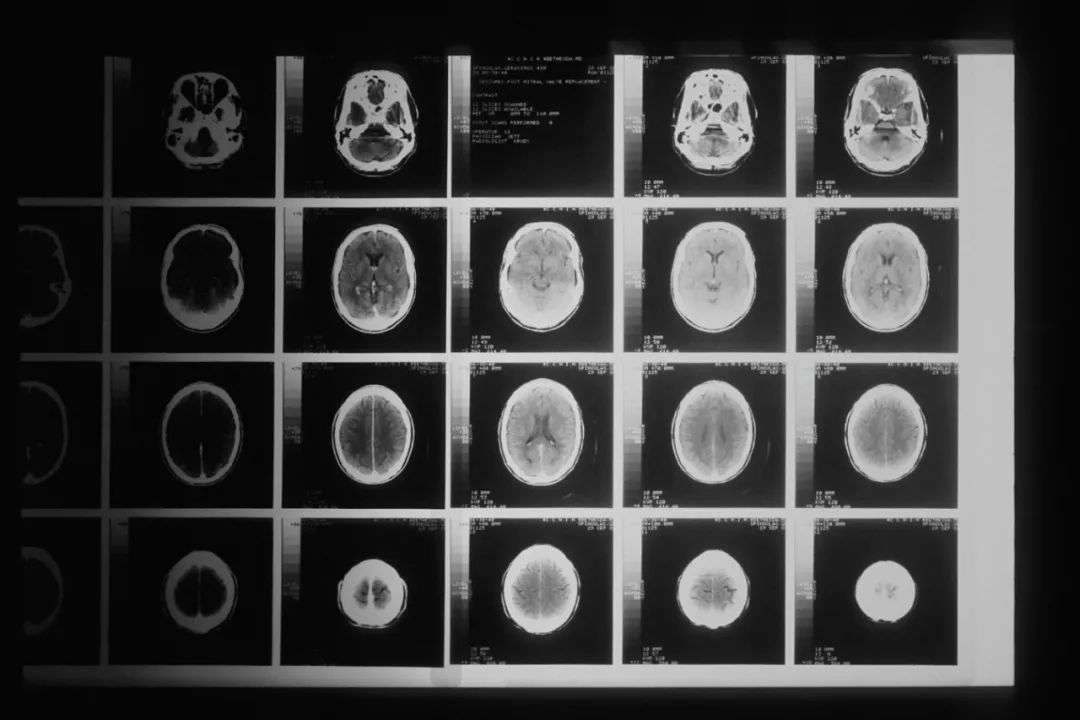

Tamar Robotics的业务重心是神经外科手术机器人。这种机器人是首批为脑外科开发的机器人系统之一,为医生提供一种更安全、微创的工具来去除脑部肿瘤和血栓。

该技术目前正在像猪这样的大型动物身上进行测试,它由一个微小的移动机器人针组成,通过射出水流破坏大脑中的肿瘤和血凝块。针头通过头部的一个小切口插入,然后外科医生在成像软件的协助下远程控制它。

同时,系统还可以提供持续扫描的集成超声波,有助于实时引导针头。这一点很重要——因为在手术过程中大脑图像会随着组织区域的切除而不断变化,因此很难依赖MRI和其他扫描的术前图像。

神经外科手术一直存在手术空间小、定位困难等痛点。因此,医疗影像的加成对于神经外科机器人而言,比起其它类型的手术机器人更加重要。可以说,做好影像定位的第一步,一款神经外科手术机器人才算跨入了成功的门槛。